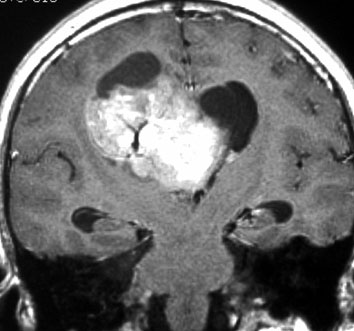

20代の男性の神経細胞腫です。側脳室の中のとても大きな腫瘍です。上段はガドリニウムという造影剤を入れた時のMRIです。下段の中央はCTですが,石灰化が見られます。脳外科の先生には,この脳室内腫瘍は一見transcallosal approach(経脳梁到達法)という手術で取れるように見えるかもしれませんが,そうではなくて,脳室の壁とくに上壁と側壁にくっついているのでなかなか取れません。この患者さんの場合は右の頭頂葉というところからtranscortical approach(経皮質到達法)で全摘出しました。後遺症もなく再発もなく術後10年が過ぎています。全部とれれば治ってしまう腫瘍です。